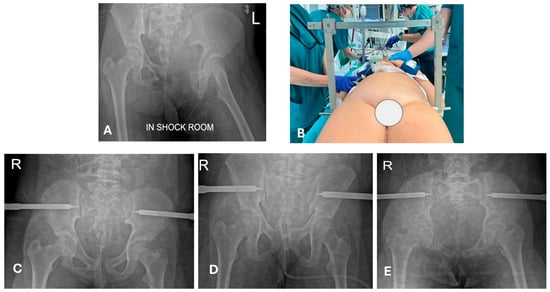

- In the age-group 15–17 years, 23/23 (100%) cases were treated with temporary external fixation (ExFix);

- In the age group 12–14 years, 9/14 (64%) cases were treated with ExFix, and 5/14 (26%) cases were treated with elastic stable intramedullary nails (ESIN);

- In the age group 5–11 years, 1/5 (20%) cases were treated with ExFix, and 4 cases were treated with ESIN;

- In the age group 0–4 years, 2/4 (50%) cases were treated with ESIN, and 2/4 (50%) cases were treated with a hip spica cast.